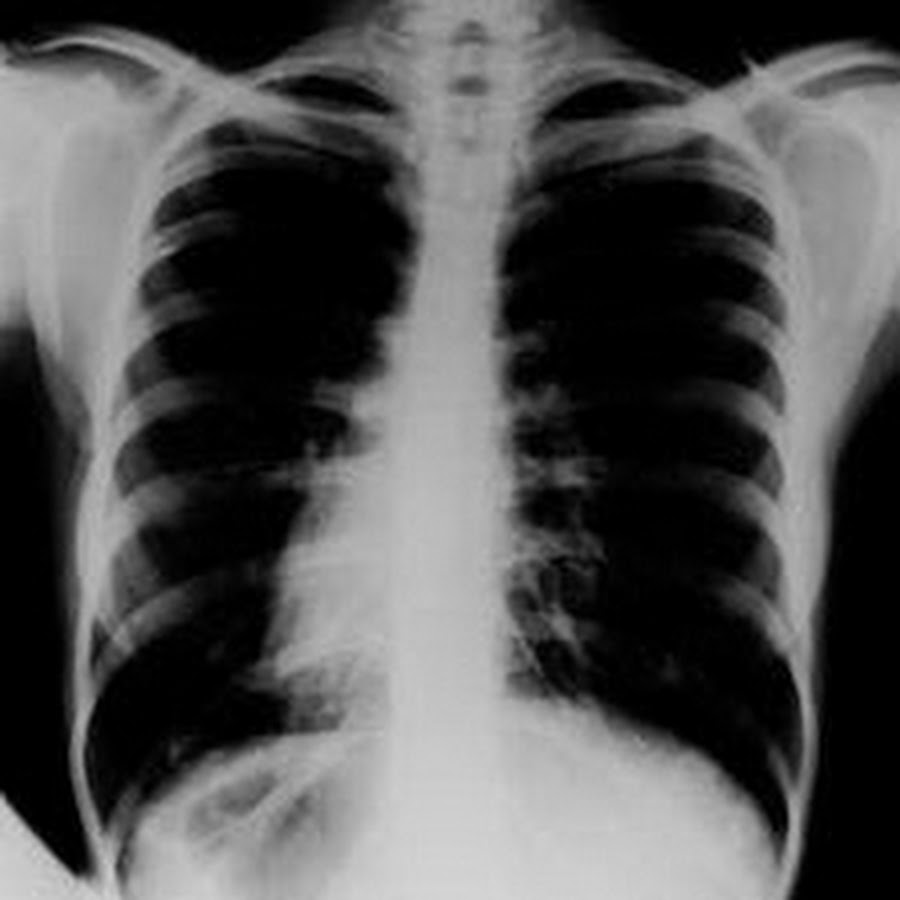

Здоровье легких: Рентген и курение